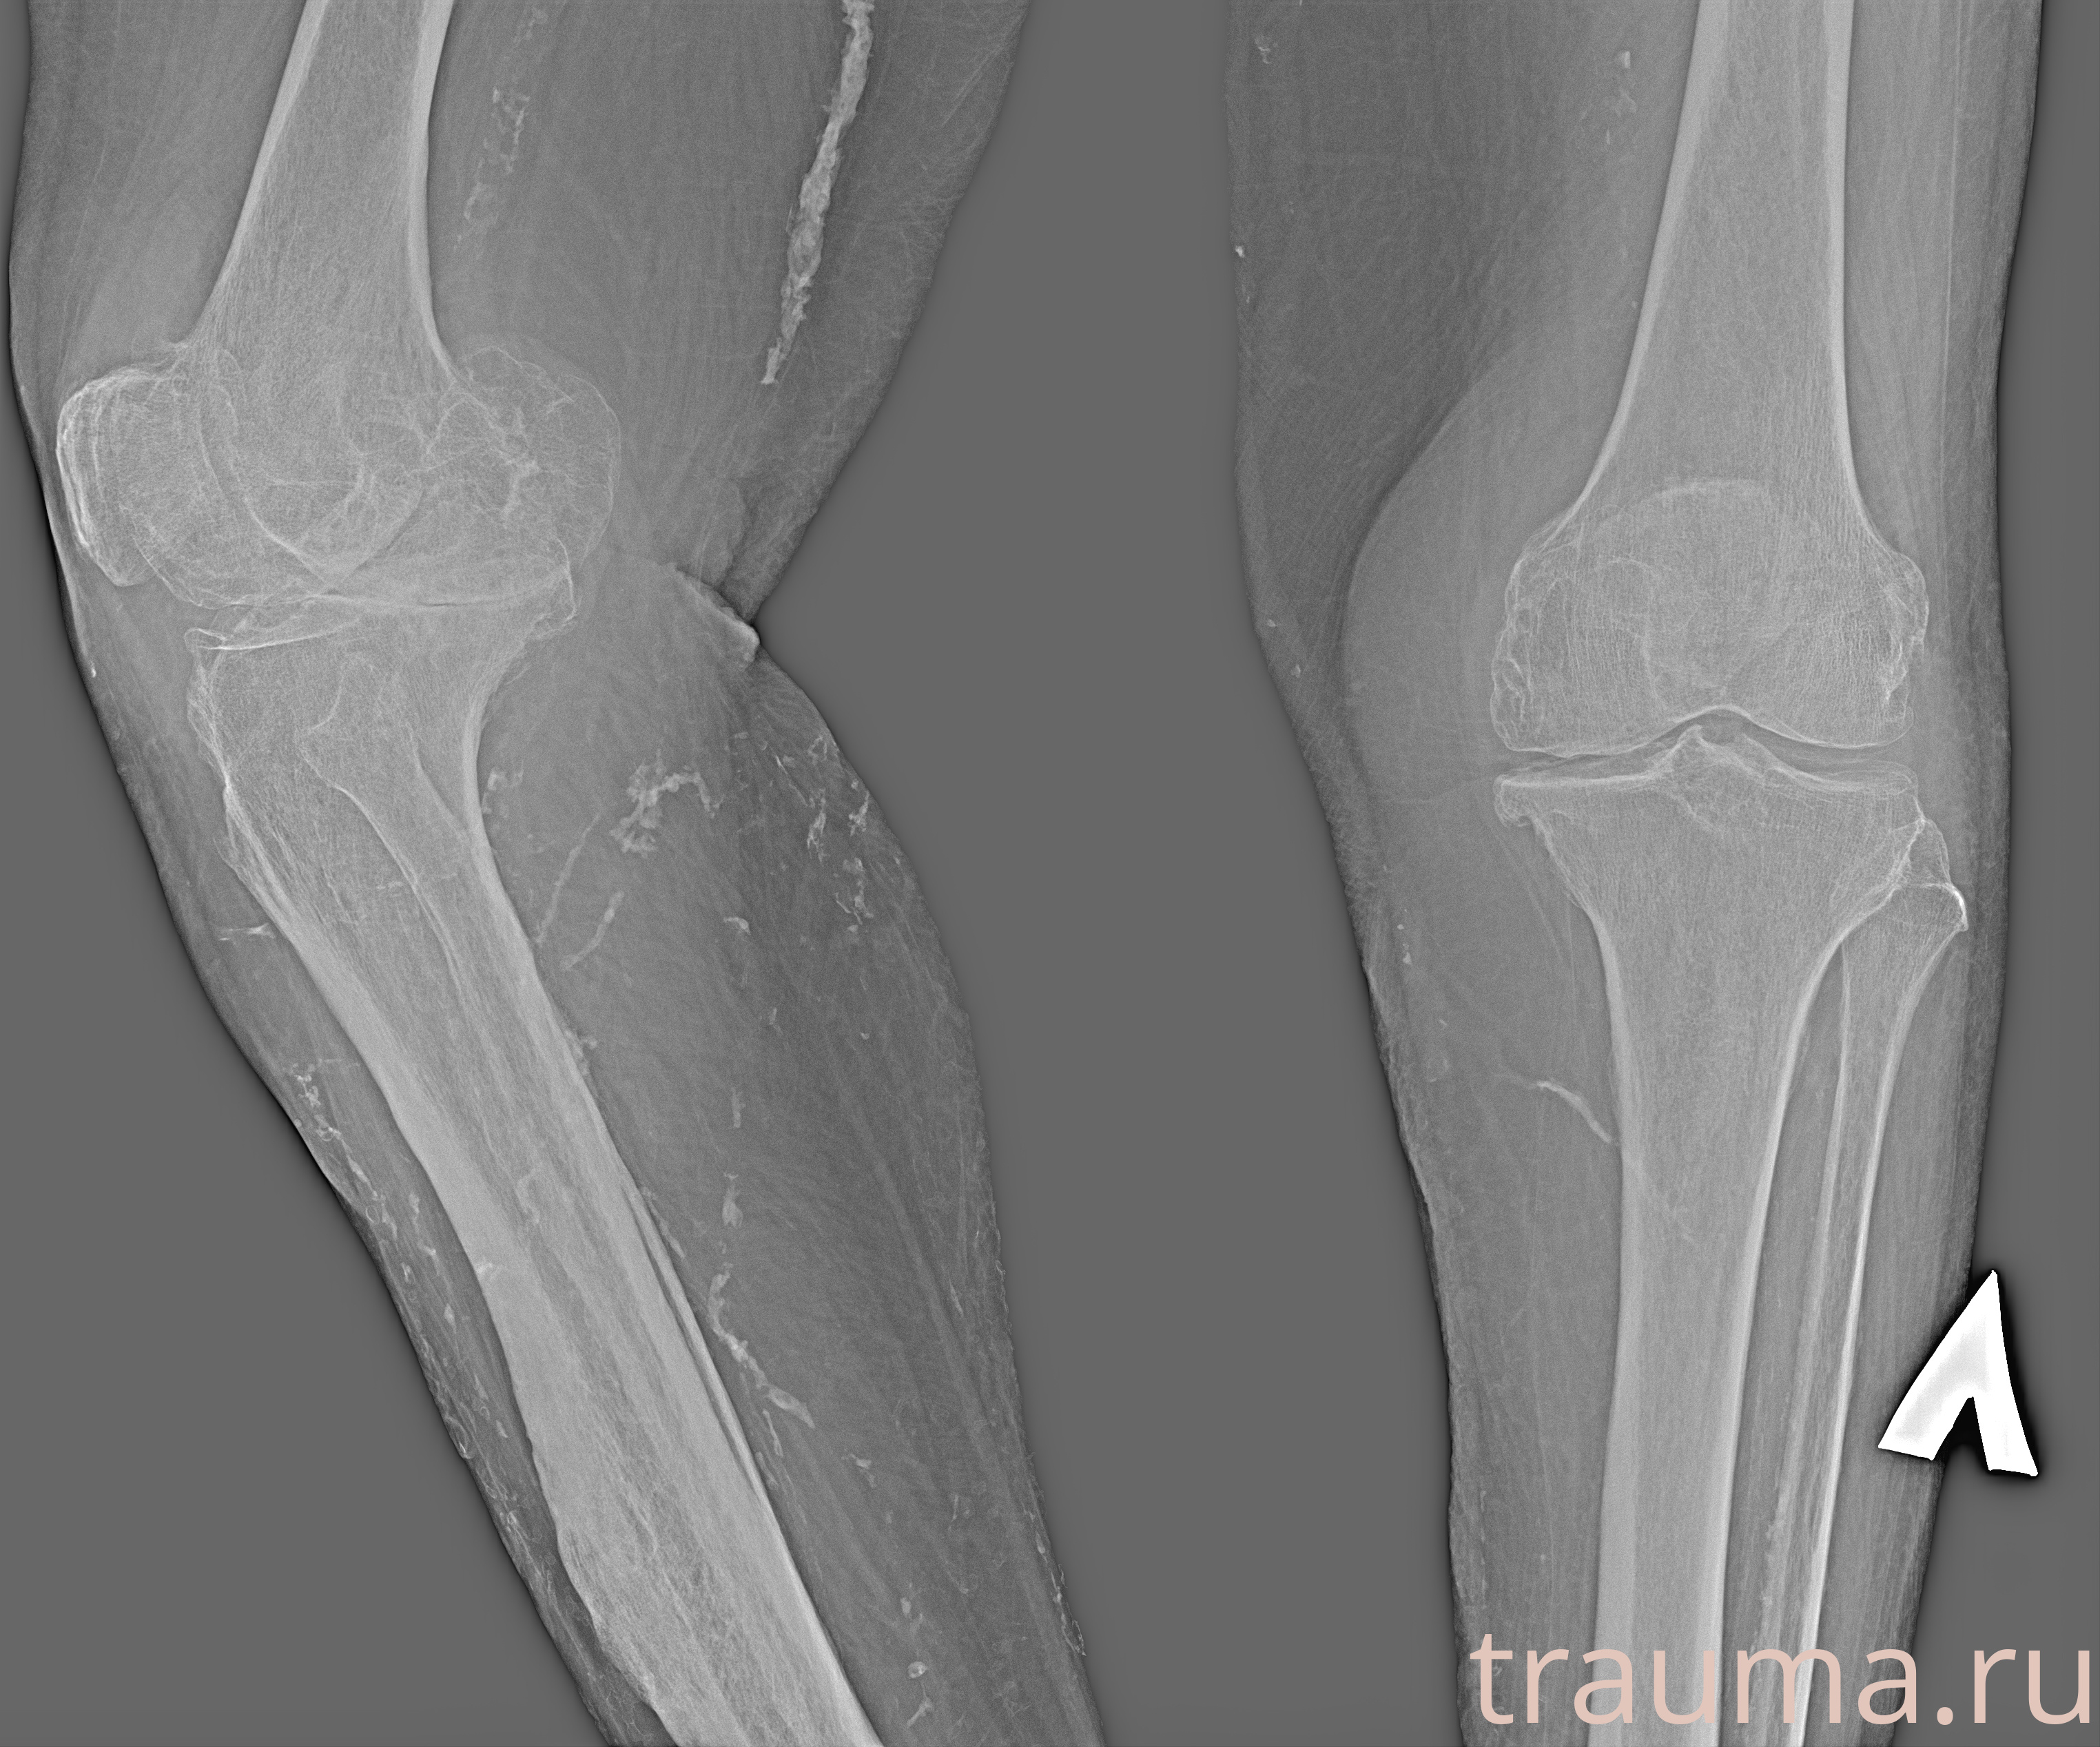

Рентгенограммы

Рентген на дому: по вашему адресу приезжает врач-рентгенолог, травматолог-ортопед с мобильным рентгеновским аппаратом, проводит диагностику травмы или заболевания, делает необходимые рентгенограммы, дает рекомендации по дальнейшему лечению. Получить качественные снимки в домашних условиях возможно благодаря уникальной методике, разработанной МосРентген Центром для института  Склифосовского

Яркость: 1   Контраст: 1   Инвертировать: 0 Увеличение: 1

Перетаскивайте мышь вверх/вниз для контраста, влево/право для яркости. Прокрутка колесом изменяет масштаб. Нажмите Сбросить для возврата к исходному изображению. При увеличении держите мышь в той области, которую хотите рассмотреть.